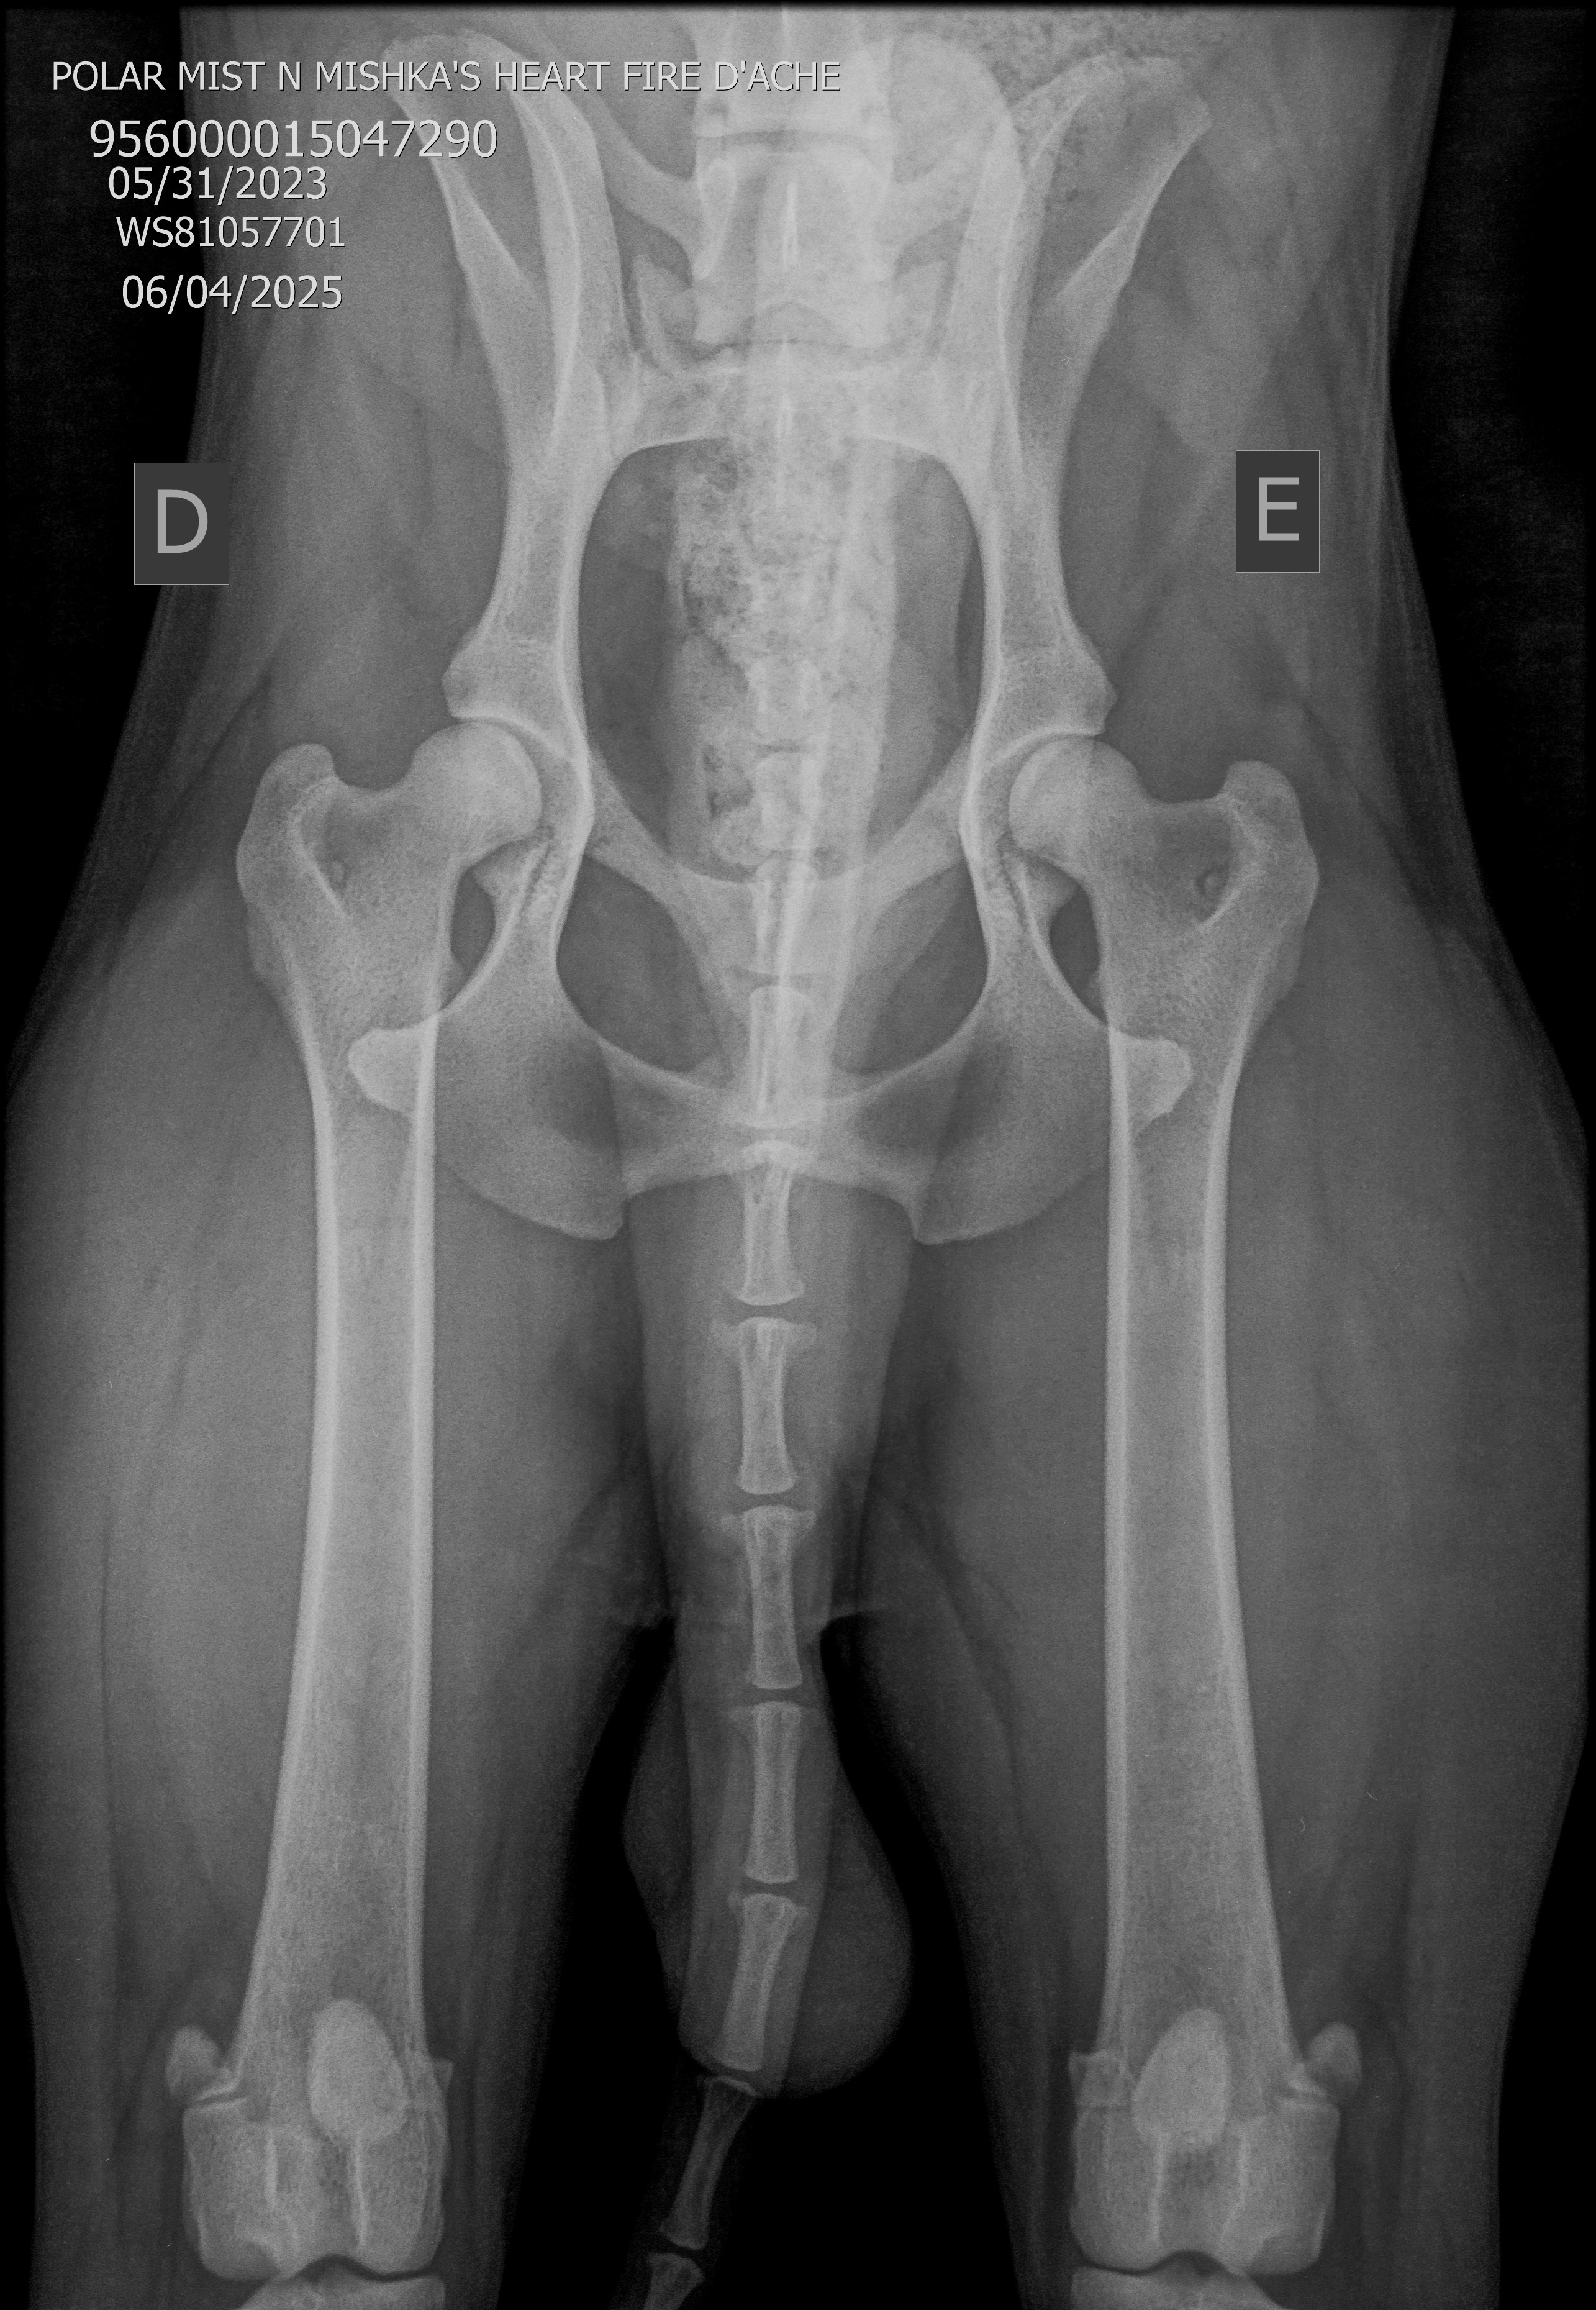

- HD 12 MESES – HD -+/- A